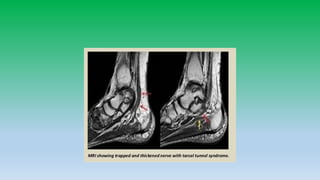

Tarsal tunnel :

• Fibro-osseous tunnel located on medial side of ankle and hind foot

extending from medial malleolus to navicular bone.

• Talus and sustentaculum tali forms lateral wall and medially by flexor

retinaculum and abductor hallucis muscle.

• Contents: Posterior tibila N/A/V, tibialis posterior, FDL, FHL tendons.

• Syndrome can arises from abnormalities intrinsic or extrinsic to

tunnel.

• 29. Tarsal tunnel : • Fibro-osseous tunnel located on medial side of ankle and hind foot extending from medial malleolus to navicular bone. • Talus and sustentaculum tali forms lateral wall and medially by flexor retinaculum and abductor hallucis muscle. • Contents: Posterior tibila N/A/V, tibialis posterior, FDL, FHL tendons. • Syndrome can arises from abnormalities intrinsic or extrinsic to tunnel.